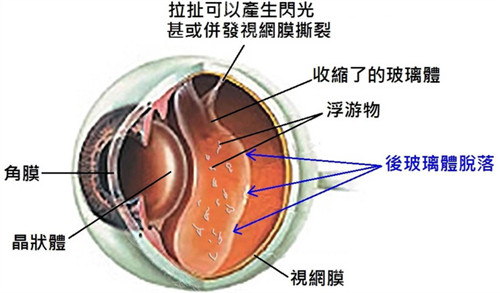

而对于病情复杂的视网膜脱落,如伴有玻璃体混浊、牵拉等情况,玻璃体切割视网膜复位联合手术是常用的治疗方式。

这种手术对技术要求高,需要特殊的设备及术后护理。此外,渗出性视网膜脱离主要以治疗原发病为主。